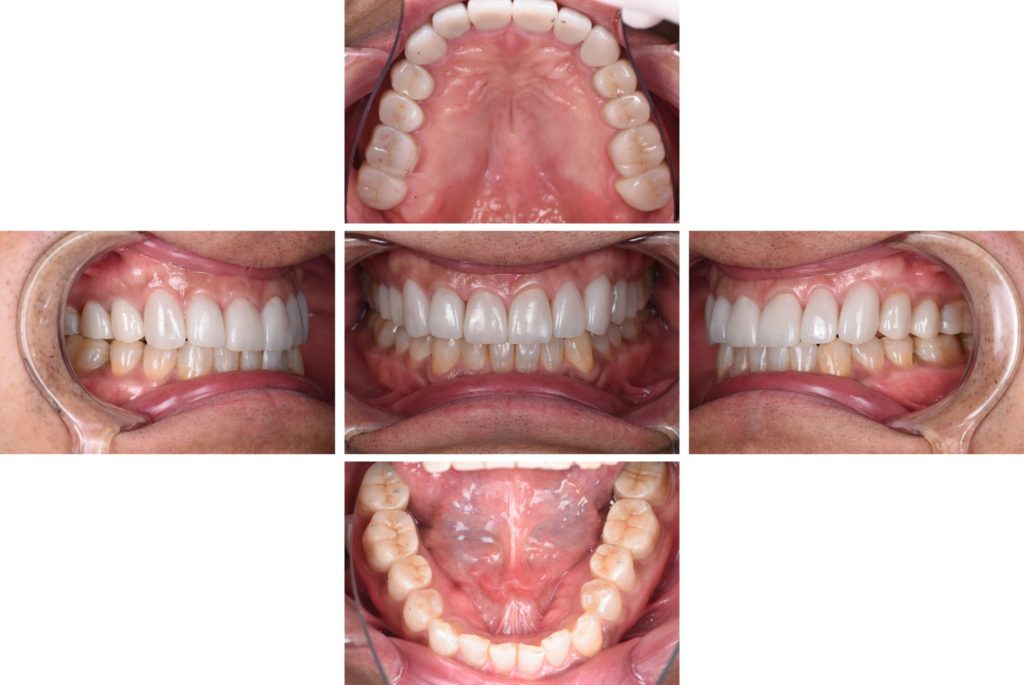

デジタルによるスマイルデザインから接着修復にて全顎的に修復した症例(インビザライン、セラミック、デジタル)

After

術前、術後比較。歯の形態、色調の改善が認められます。